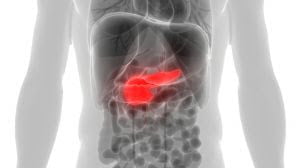

Responsável por cerca de 1% de todos os tipos de câncer diagnosticados e por 5% do total de mortes causadas pela doença no Brasil, o câncer de pâncreas é o sétimo câncer mais letal no país. São registradas no Brasil, anualmente, quase 12 mil mortes, segundo o Atlas de Mortalidade do Instituto Nacional de Câncer (INCA). Conforme o Globocan, base de dados da Organização Mundial de Saúde, houve 495 mil novos casos de câncer de pâncreas apenas em 2020 no mundo. No mesmo ano, 466 mil pessoas faleceram devido à doença, dado que corresponde a 7ª causa de mortalidade por câncer no planeta.

Isso acontece porque a maioria dos pacientes tem acesso ao tratamento nos estágios mais avançados. No início, o câncer no pâncreas apresenta sintomas pouco distinguíveis. Comparativamente, a taxa de sobrevida após cinco anos do diagnóstico é inferior a 5% nos casos de doença avançada (metástase). Com diagnóstico precoce, de acordo com o levantamento SEER, do Instituto Nacional de Câncer dos Estados Unidos, a taxa de sobrevida em cinco anos salta para 43,9%.

Assim, a Sociedade Brasileira de Cirurgia Oncológica (SBCO) reforça e estimula as estratégias para aprimorar o diagnóstico precoce. Para evitar que as pessoas cheguem aos serviços de saúde apenas nos estágios avançados da doença, a investigação estratégica é essencial: “Infelizmente, o câncer de pâncreas é difícil de diagnosticar precocemente porque os sintomas iniciais podem ser inespecíficos, como dor abdominal, perda de peso e fadiga”, explica o cirurgião oncológico Heber Salvador de Castro Ribeiro, presidente da SBCO.

Em relação ao tratamento, é necessário fazer uma análise criteriosa sobre o estágio da doença, da localização do tumor, da saúde geral do paciente e de outros fatores biológicos. “A cirurgia é o tratamento mais comum. A remoção do tumor pode afetar uma parte do pâncreas, o duodeno, a vesícula biliar e parte do estômago e, quanto mais inicial for a descoberta, mais a cirurgia oncológica segura é efetiva”, explica Héber Salvador. Além disso, outros tratamentos não-cirúrgicos, indicados caso a caso, também contribuem para aumentar a sobrevida dos pacientes, como a quimioterapia, radioterapia e imunoterapia.

Os principais fatores de risco para câncer de pâncreas são histórico familiar, idade avançada, tabagismo e obesidade. Se uma pessoa apresentar um ou mais desses fatores de risco e apresentar sintomas vagos e inespecíficos, é importante que ela consulte um médico para avaliação.

Além disso, os médicos podem solicitar exames de triagem para detectar o câncer de pâncreas em pessoas que apresentam alto risco, como aquelas com histórico familiar de câncer de pâncreas ou síndrome de pancreatite hereditária. Outras avaliações que podem ser incluídas são exames de imagem, como tomografia computadorizada e ressonância magnética, ou testes de sangue para marcadores tumorais, incluindo biópsia líquida. Embora a relação com o diabetes não esteja completamente esclarecida, há um ponto a se prestar a atenção: pacientes que iniciam quadro de diabetes súbito em idades mais avançadas ou que tem seu quadro de diabetes descompensado sem outra causa aparente devem realizar exames para descartar a presença da neoplasia.